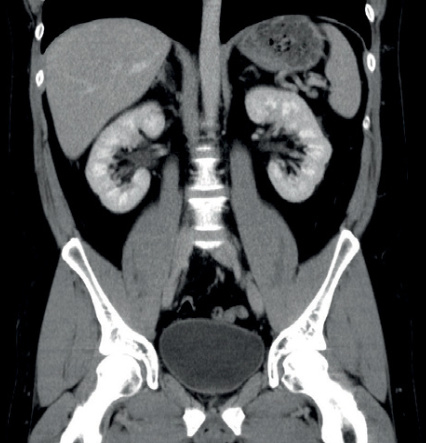

Image

Lungendarstellung